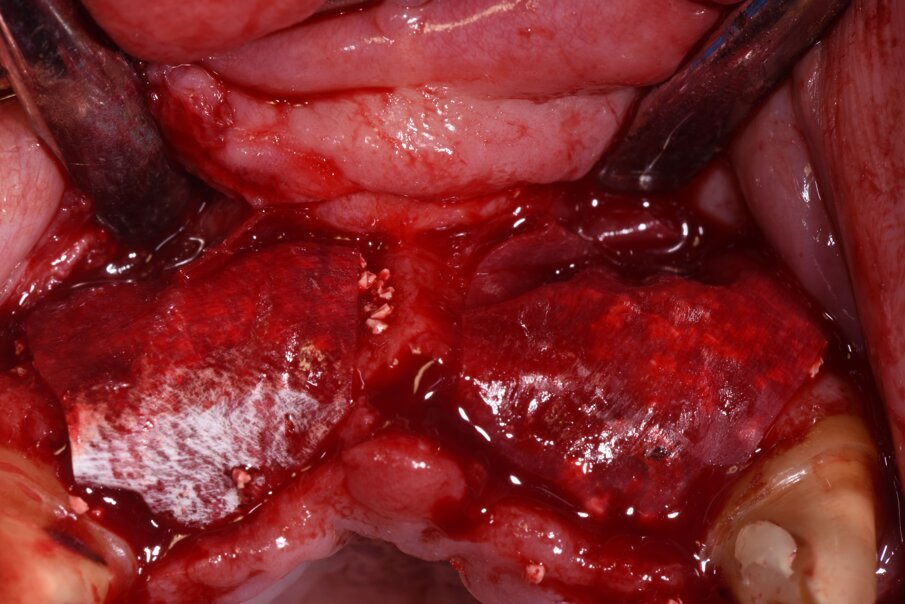

La rigenerazione ossea è stata ottenuta secondo l’impiego di biomateriale di origine bovina demineralizzato e stabilizzato con una membrana a lento riassorbimento in pericardio nativo fissata con dei chiodini in titanio (Fig. 23). Com’è noto la stabilità dell’innesto è un requisito indispensabile per ottenere una reale rigenerazione ossea stabile nel tempo. Dopo 4-6 mesi si effettua una radiografia di controllo eseguendo successivamente un opercolo perimplantare. In questo caso data la lieve deiscenza presente si è optato per l’impiego di un diatermocoagulatore per limitare il danno biologico ai tessuti limitrofi e mantenere inalterata la rivascolarizzazione della sede, inoltre non essendo un materiale metallico ma bensì ceramico, l’eventuale contatto viene disperso e non assorbito dall’impianto (Fig. 24). Data l’ottima stabilizzazione funzionale e volendo contenere i costi viene realizzata un’impronta digitale dell’arcata col primo provvisorio in situ e alla sua rimozione un’impronta dell’intera arcata con e senza gli scan body implantari (Fig. 25). Per mantenere l’opercolo ottenuto si utilizzano delle cappette di guarigione sempre in Zirconia che serviranno anche per stabilizzare i tessuti perimplantari (Fig. 26). In laboratorio, l’odontotecnico su nostra indicazione potrà elaborare i file ricevuti, valutando la possibilità di avvitare direttamente il manufatto, solo in caso di forte disparallelismo si opterà per la cementazione. Definita la procedura, verrà realizzato solo il provvisorio su impianti modificando il primo provvisorio che sarà riposizionato dopo il sezionamento dei quadranti (Figg. 27, 28). Dopo il posizionamento del nuovo provvisorio rileviamo una nuova impronta studio (Fig. 29) che analizziamo col software dedicato dello scanner digitale utilizzato.

Fig. 23_Per ottimizzare l’azione chirurgica a quella estetica abbiamo progettato una rigenerazione ossea volta ad aumentare il volume vestibolare, utilizzando un sostituto osseo a lento riassorbimento e delle membrane in periostio sottili e riassorbibili fissate con chiodini non riassorbibili.